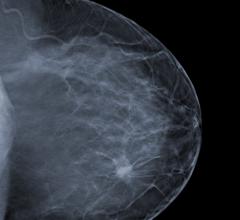

A study conducted by Mayo Clinic and published in the AJR has clinically confirmed that Molecular Breast Imaging (MBI) yields superior imaging and low radiation exposure for women with dense breast tissue, which can affect up to 40 percent of the female population.

Gamma Medica announced the company now offers Philips MicroDose SI, the first full-field digital mammography (FFDM) system that supports single-shot, non-invasive spectral imaging, as a complement to its market leading LumaGEM Molecular Breast Imaging (MBI) system. LumaGEM is a highly effective and cost-efficient technology for detecting breast cancer in patients with complex mammograms and dense breast tissue. The agreement with Philips will enable Gamma Medica to provide breast imaging suites with the option to purchase both technologies and offer the most advanced and safest commercially available dense breast solution for women. Philips will continue selling MicroDoseSI directly to customers.